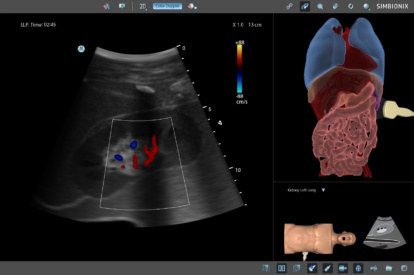

Ultrasound Mentor accelerates the development of basic to advanced technical and cognitive skills, by providing not only the probe manipulation training, but also a didactic environment enabling structured, self-guided learning including step-by-step instructions and educational aids such as 3D anatomical map and probe positioning assistant, all backed up with our progress monitoring tool MentorLearn.

- Advanced diagnostic tools, including Color Doppler, CW, PW, M-mode, and measurements

EFAST and RUSH MODULE